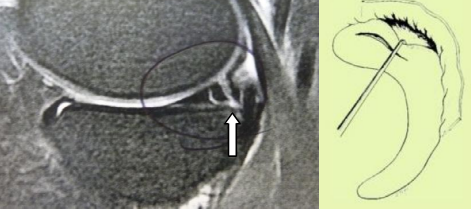

- Les lésions associées à une rupture récente du LCA, sont toujours périphériques à type de désinsertion ménisco-synoviale. Ces lésions situées en zone rouge ont un fort potentiel de cicatrisation spontanée. Elles pourront bénéficier dans le même temps que la réparation du LCA, d'une abstention thérapeutique si elles sont stables ou d’une réparation par suture si elles sont instables (voir plus loin).

Figure 3 : lésion périphérique de la corne postérieure du ménisque interne en vue IRM et en vue arthroscopique (le crochet teste la stabilité de la désinsertion)

Sur genou laxe, les lésions méniscales sont le plus souvent représentées par une désinsertion périphérique du segment postérieur du ménisque interne. Malgré leur potentiel de cicatrisation spontanée, elles doivent être diagnostiquées et traitées. L’arthroscopie permet d’évaluer la taille et la stabilité de la lésion. Le ménisque devra être suturé, si la désinsertion fait plus de 10 mm de large ou si le ménisque désinséré peut être mobilisé sous le cond yle (Figure 3). Dans le cas contraire, un simple avivement de la lésion suffit pour permettre la cicatrisation. Que la laxité soit récente ou ancienne, il est souhaitable de réaliser dans le même temps que la suture méniscale, une réparation du LCA car les chances de cicatrisation sont de 90%.